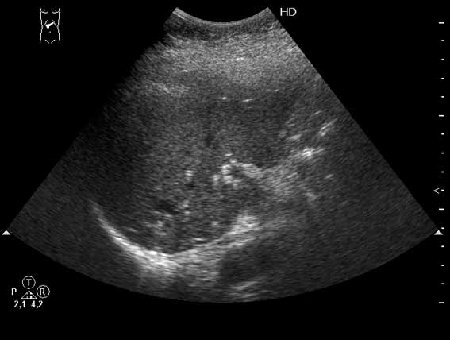

Внутрипротоковые гамартомы

Иногда встречается.

Как трактовать?

Быть может кто-либо знает о морфологическом субстрате подобного явления?

- 1.jpg (17.38 КБ) 6296 просмотров

- 2.jpg (11.96 КБ) 6299 просмотров

- 3.jpg (10.79 КБ) 6296 просмотров

Получил данные за то, что, видимо, это мелкие конкременты в протоковой системе.

Доводы:

1) Эхогенные структуктуры дают твинклинг-артефакт (twinkling), характерный, например, для кальцийсодержащих образований.

2) Все пациенты, у которых наблюдалась подобная картина страдали ЖКБ, у всех был удален желчный пузырь.